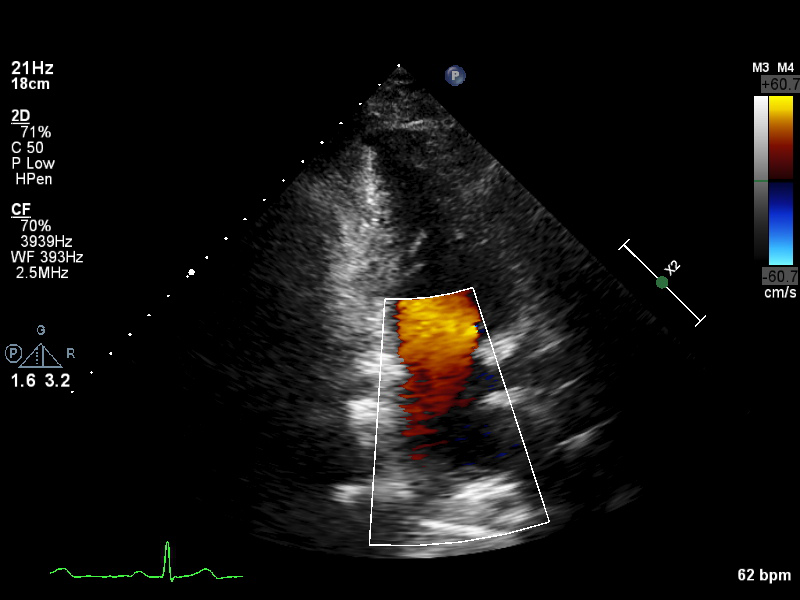

ImageView NameDescription

a5ch-outflow a5ch-outflow A5CH including LVOT; may lack full depth or has LVOT colour